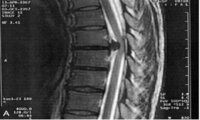

胸椎黄色靭帯骨化症に胸椎椎間板ヘルニアを合併した1例 江川 誠一郎 , 田中 英俊 , 遠藤 健司 , 小林 浩人 , 田中 惠 , 鈴木 秀和 , 山本 謙吾 関東整形災害外科学会雑誌 39(5), , 胸椎椎間板ヘルニア、胸椎後縦靭帯骨化症、胸椎黄色靭帯骨化症などがJun 30, · 「 腰椎椎間板ヘルニアの病態と症状」 ①胸椎伸展エクササイズ(肩甲骨も使いながら) 基本的に始めの段階は、椎間板に負担がかからないように腰を前に曲げる姿勢は避けます。胸椎椎間板ヘルニアの発生頻度は報告者により差は あるが,全 脊椎ヘルニアの1%前 後と言われている1) 当科においても平成元年より調査したところ07%で あった 胸椎椎間板ヘルニアに対する手術法として大別し, 前方法(経 胸腔法,経 胸膜外腔法,胸 骨縦割法

胸椎 椎間板 ヘルニア-胸椎椎間板ヘルニアの原因 椎間板が突出することにより発症するのが胸椎椎間板ヘルニアです(胸部は頸椎・腰椎と比較すると稀な病態)。 変形性胸椎症の原因 加齢性変化によって脊椎が変形し脊髄を圧迫するのが変形性胸椎症です。 症状Th11/12胸椎椎間板ヘルニアに対して経皮的胸椎内視察下胸椎椎間板摘出術(PETD)を施行した1例 伊東 孝浩 , 吉兼 浩一 , 仲西 知憲 , 岡田 文 , 大江 健次郎 , 西井 章裕 , 山口 司 整形外科と災害外科 62(4), ,

多椎間に及ぶ胸椎椎間板ヘルニアに対し後方除圧と後彎軽減を施行した1例 臨床雑誌整形外科 60巻1号 医書 Jp

第2 3胸椎椎間板ヘルニアの1例 臨床整形外科 32巻1号 医書 Jp

胸椎椎間板ヘルニアとは 運動器の病気